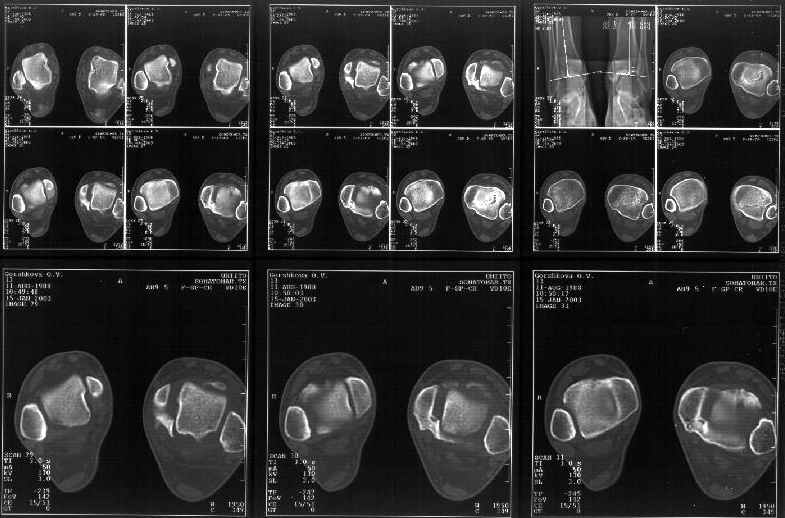

Я пометил линию перелома черной линией.

К сожалению на последних присланных срезах КТ нет более низкого, через таран, среза, который был на прежнем майле. На XR я попытался показать

стержень внутри сустава и то как он раскрывает пространство между тараном и мед. малеолом.

Сегодня пациентке сделали сравнительную КТ. А ксиальные и Фронтальные срезы приложены. Ваше мнение?

Аксиальные

На КТ я попытался изобразить скромными своими способностями (А)- место перелома, (С)- нормальный суставной зазор меж тараном и тремя его маллеолами. (В)- образовавшийся в результате перелома широкий раза в три зазор, позволяющий, по-моему, сублюксацию тарана при ходьбе. В свете данных КТ, критически важных, я бы предложил вертикальную остеотомию места перелома

задне-внутренним подходом и фиксацию мед. маллеола прижатым к тарану с помощью тонкого compression screw. После этого гипсовый сапожок и немедленное расхаживание ноги.